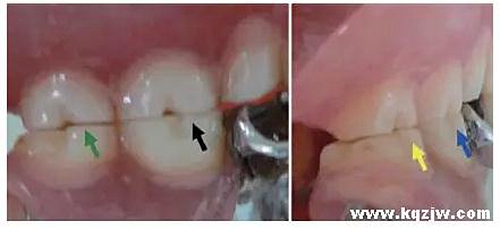

其包括①頰舌面塑形,以改善上下牙的覆(牙合)覆蓋關(guān)系(圖8);②近遠(yuǎn)中向塑形,以改善鄰接關(guān)系或外展隙形態(tài)(圖9)。

①形成一定的溝窩結(jié)構(gòu),例如頰溝、舌溝,以改善食物溢出通道;②消除銳邊、銳緣、銳棱等異常磨耗所形成的微小結(jié)果(圖10)。

咬合接觸點(diǎn)的分布

通過(guò)調(diào)改咬合紙檢測(cè)所顯示的咬合接觸點(diǎn),將正中咬合時(shí)的接觸引導(dǎo)到支持尖牙尖壁上,其中下頜后牙以頰尖舌斜面為主,上頜后牙以舌尖頰斜面為主(圖11)。盡量使咬合接觸點(diǎn)廣泛分布,力度(著色程度)均衡。